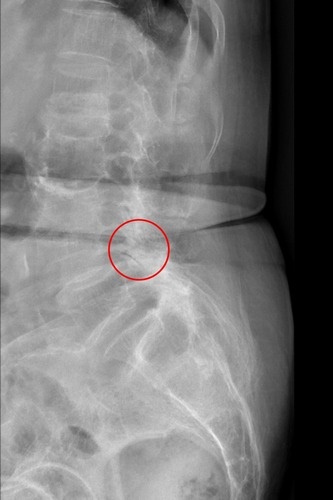

左圖:經X光檢查發現郭奶奶腰椎滑脫。

經考慮患者意願,在與家屬溝通後,由麻醉團隊為患者安排心臟超音波、頸部超音波、神經傳導等檢查評估風險,洪祥益主任帶領團隊於十月底為患者進行微創腰椎融合手術,利用釘子將滑脫的脊椎矯正歸位,並把骨刺清除乾淨。 洪祥益主任指出,傳統手術需要將肌肉剝離,傷口較大、術後恢復較慢,手術感染風險較高,且因手術傷口疼痛,病人往往無法立刻下床行動,需要臥床休養,對於高齡患者而言,長時間的臥床還可能引起肺炎等合併症。有別於傳統手術,微創融合手術則可以保留肌肉,利用撐開器順著肌肉紋理建立手術路徑,減少組織破壞,因此傷口小、術後疼痛感低,有助於加速恢復。待麻醉退掉,郭奶奶於手術隔日即可自行下床行走,不僅手術傷口不痛,也不再腿疼、腳麻,順利於五日後出院返家。